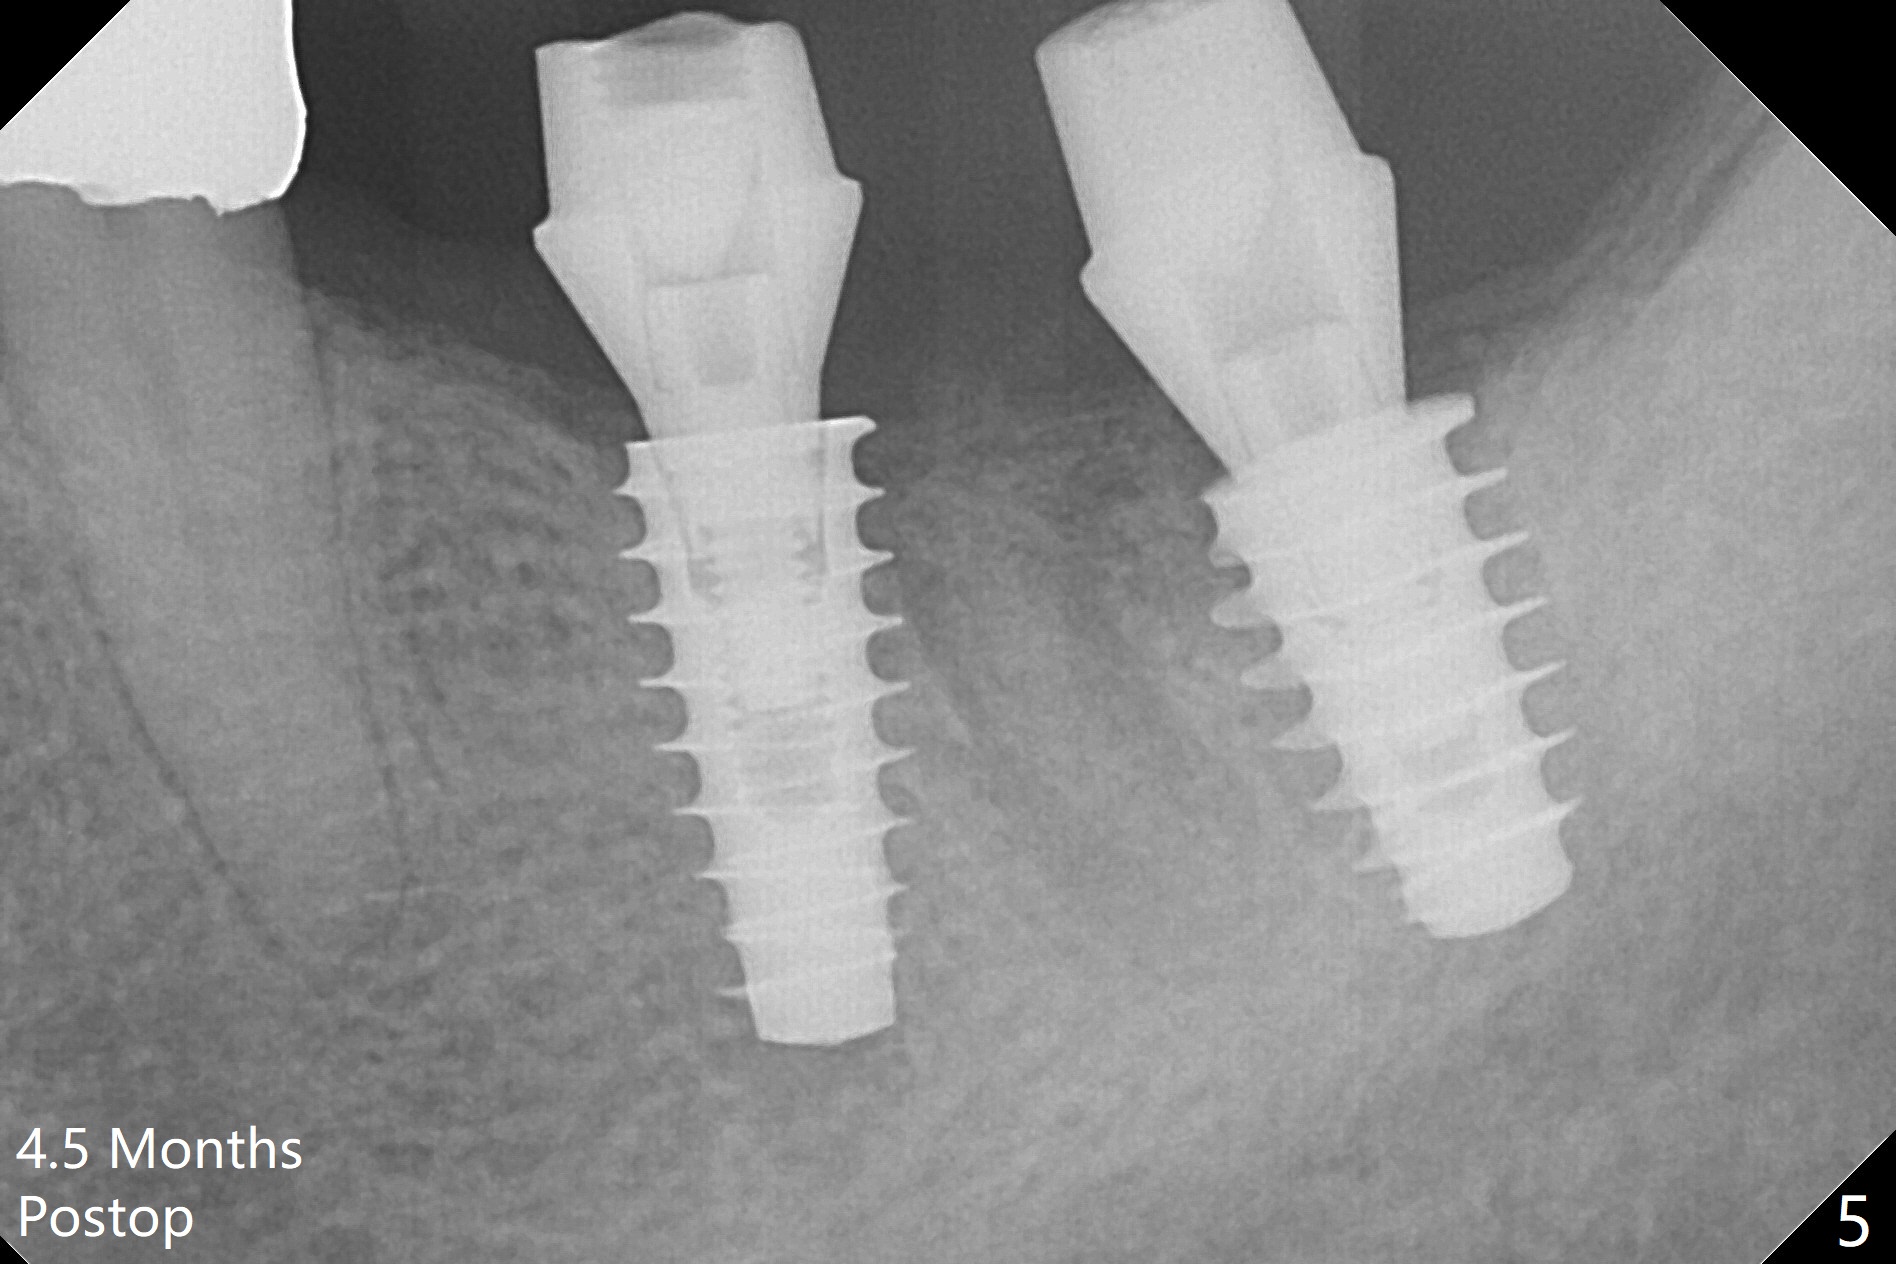

A drawback of placing an implant in the distal socket of the 2nd lower molar is closer to the Inferior Alveolar Canal.  The implants seem to have osteointegrated 4.5 months postop (Fig.5).  While the ridge at #19 appears to be wider than preop (as compared to Fig.1), that at #18 seems to be atrophic 5 months postop (Fig.6 * (1 week post cementation)).  The distal implant placement at #19 may increase possibility of abutment screw loosening during functioning (Fig.7 *).  When the patient returns for periodic exam 1.5 months post cementation, loose contact between the implant crowns is noted (Fig.8).  The bony trabeculae form between the 2 implants crestally 12 months postop, i.e., 7 months post cementation (Fig.9).  The loose contact between the 2 implants is corrected 14 months post cementation.